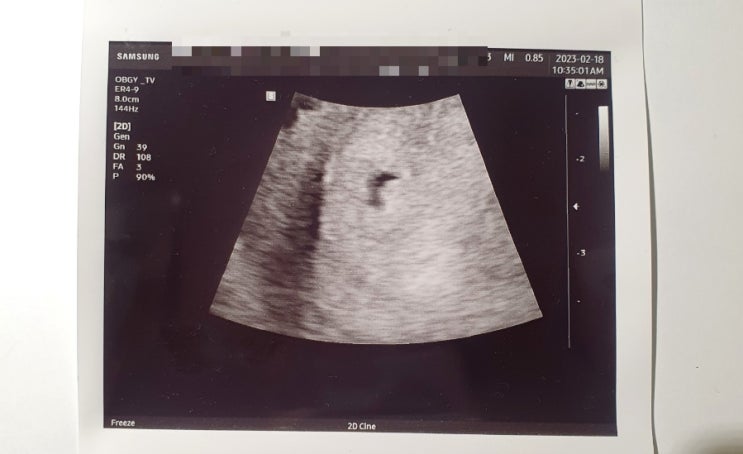

[임신일기] 임신 5-7주. 산부인과 첫 방문 (찌그러진 아기집. 자궁근종. 유산기 )

5주 0일. 첫 산부인과 진료 원포테스트기로 임신 확인 후, 드디어 마지막 생리일로부터 5주차 0일이 되어 ...